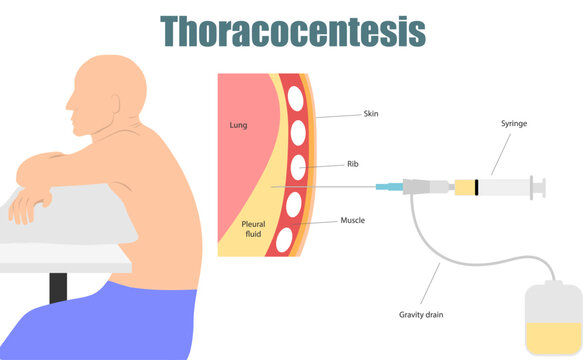

Thoracocentesis (થોરાકોસેન્ટેસીસ):

- થોરાકોસેન્ટેસીસ એ એક ડાયગ્નોસ્ટિક અને થેરાપ્યુટિક પ્રોસિઝર છે.

- જેમાં લંગ અને ચેસ્ટ વોલની વચ્ચે આવેલ પ્લુરલ સ્પેસમાંથી નીડલ અથવા પ્લાસ્ટિક કેથેટરની મદદથી ફ્લૂઇડ એસ્પીરેટ કરવામાં આવે છે અને આ પ્લુરલ ફલુઇડનું એનાલાયસીસ કરવામાં આવે છે.

- નોર્મલી પ્લુરલ સ્પેસમાં થોડી માત્રામાં પ્લુરલ ફ્લૂઇડ આવેલું હોય છે. જો વધારે માત્રામાં આવેલ હોય તો તે કોઈ ડીઝીસ કન્ડિશન ઇન્ડિકેટ કરે છે.

- આ પ્લુરલ ફ્લુઇડને ગ્રામ સ્ટેઇન કલ્ચર અને સેન્સિટીવિટી, એસિડ ફાસ્ટ સેન્સિટીવિટી અને કલ્ચર, ડિફરન્ટ સેલ કાઉન્ટ, સાઇટોલોજી PH, સ્પેસિફિક ગ્રેવિટી અને ટોટલ પ્રોટીન માટે સ્ટડી કરવામાં આવે છે.

- આ પ્રોસિજર અલ્ટ્રાસાઉન્ડના ગાઇડન્સ હેઠળ કરવામાં આવે છે.